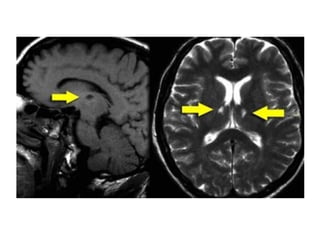

Lacunar infarcts

• Lacunar infarcts are small infarcts in the deeper parts of

the brain (basal ganglia, thalamus, white matter) and in

the brain stem.

• Lacunar infarcts are caused by occlusion of a single

deep penetrating artery.

• Lacunar infarcts account for 25% of all ischemic strokes.

• Atherosclerosis is the most common cause of lacunar

infarcts followed by emboli.

MR Findings

• Tl WI: Small, well circumscribed hypointense foci

• T2WI: Small, well circumscribed hyperintense foci

• FLAIR:Typically increased in signal

• DWI

o Restricted diffusion (hyperintense) if acute/subacute

o May show small lesions otherwise undetectable

• Tl C+: May enhance if late acute/early subacute

• MRA: Normal

Lacunes may be confused with other empty

spaces, such as enlarged perivascular

Virchow-Robin spaces (VRS).

The VRS are extensions of the

subarachnoid space that accompany

vessels entering the brain parenchyma.